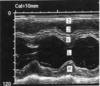

What is being measured at line #3? At what point in the cardiac cycle is this measurement performed?

RV length end diastole